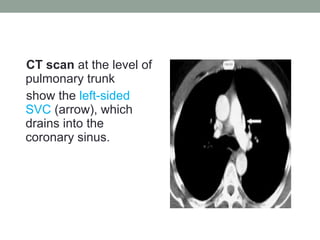

CT scan at the level of

pulmonary trunk

show the left-sided

SVC (arrow), which

drains into the

coronary sinus.